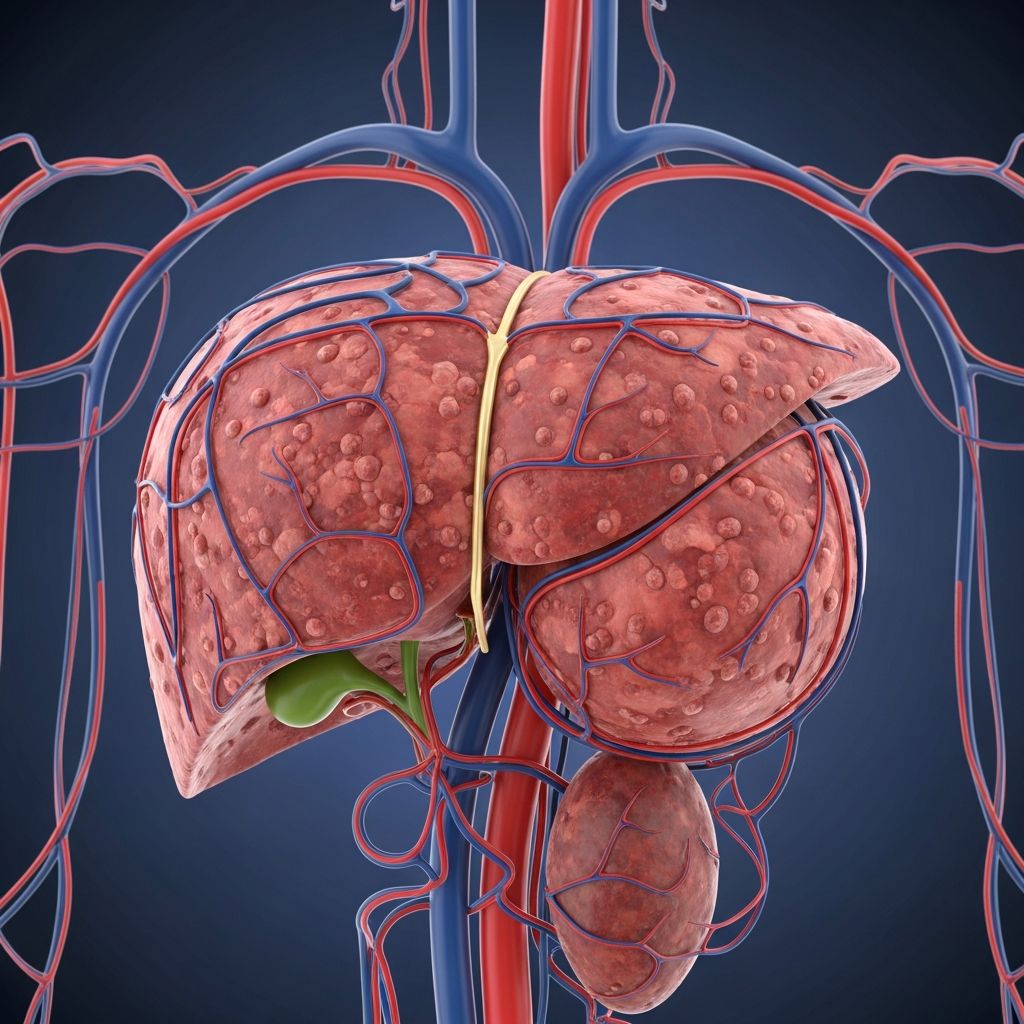

Portal hypertension occurs when blood pressure in the portal vein—the vessel that carries blood from the digestive organs to the liver—becomes abnormally elevated. This condition typically develops as a result of liver cirrhosis, chronic hepatitis, or other liver diseases that obstruct normal blood flow. The elevated pressure can lead to serious complications including the formation of enlarged veins (varices) in the esophagus and stomach, which carry a significant risk of life-threatening bleeding.

Treatment for portal hypertension aims to reduce portal pressure, prevent bleeding from varices, and manage the complications associated with the condition. A comprehensive approach often involves a combination of medical therapies, endoscopic interventions, and in some cases, surgical procedures. The specific treatment plan depends on the severity of portal hypertension, the underlying cause, and the presence of complications such as active bleeding or ascites (fluid accumulation in the abdomen).

The transjugular intrahepatic portosystemic shunt (TIPS) represents an important radiological intervention for managing complications of portal hypertension when medical and endoscopic therapies prove inadequate. During TIPS placement, an interventional radiologist creates a channel through the liver tissue that connects the portal vein to the hepatic vein, effectively bypassing the cirrhotic liver and reducing portal pressure.

TIPS is particularly valuable in managing acute variceal bleeding that is refractory to medical therapy and endoscopic procedures. It can also be used for secondary prophylaxis in patients who have failed other treatment modalities. Additionally, TIPS addresses other portal hypertension-related complications including refractory ascites and hepatic encephalopathy, though the latter complication can actually be worsened by TIPS in some patients.

The procedure involves minimal incisions and is performed under radiological guidance with local anesthesia and sedation. A stent is placed within the created channel to maintain patency. Follow-up ultrasound surveillance is essential to monitor stent function and detect dysfunction early, as stent thrombosis can occur in approximately 10-15% of patients within the first year, though modern covered stents have improved long-term patency rates.